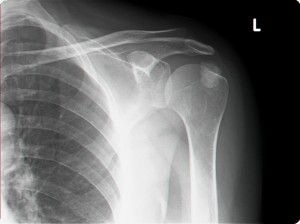

נ.מ אחרי טיפול בגלי הלם:

כתף קפואה - גלי הלם                כאב בכתף